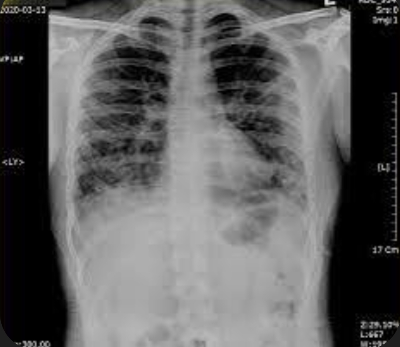

5. 폐렴 증상

폐렴 증상은 질환이 진행되면서 다양하고 심각하게 나타납니다. 주요 증상으로는 고열, 후두통, 가래를 동반한 강한 기침, 흉통, 호흡곤란, 빠른 호흡 등이 있습니다. 가래는 화농성으로 노란색이나 녹색을 띕니다.